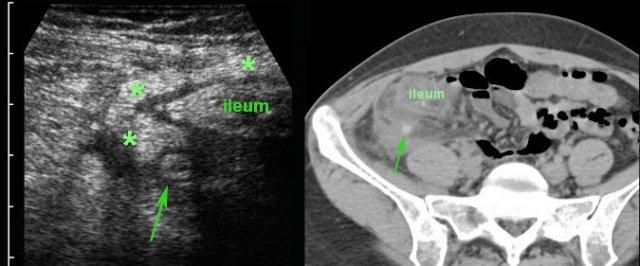

Ở bệnh nhân này, siêu âm cho thấy lượng lớn mô mỡ viêm (*) và hồi tràng dày thành, biểu hiện quá trình bao bọc thành công tình trạng thủng (sắp xảy ra) của ruột thừa (mũi tên).

Lưu ý sỏi phân vôi hóa (mũi tên trên CT) trong ruột thừa ở mức cao hơn.